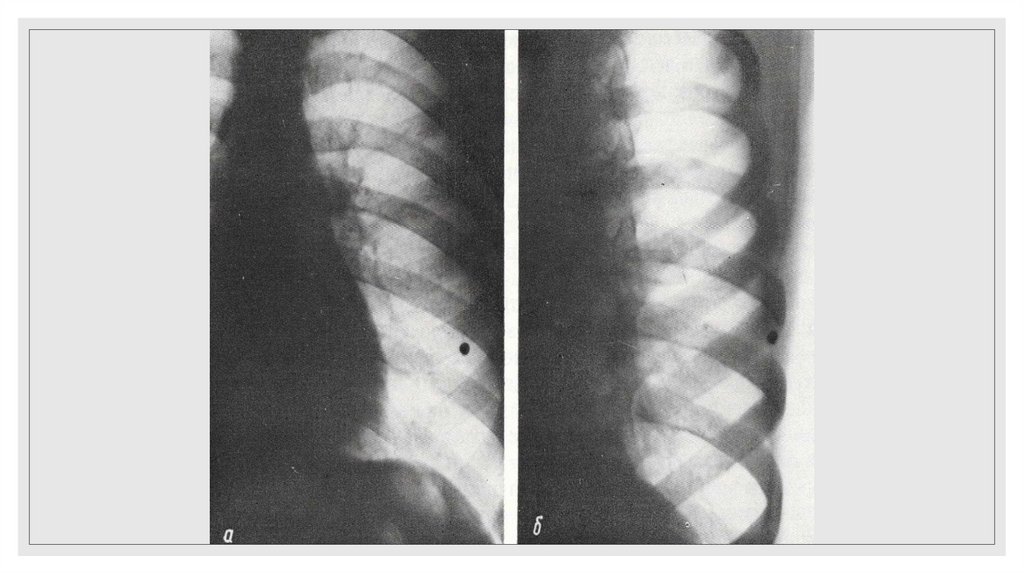

Повреждение грудного отдела аорты

25. Рентгенодиагностика переломов ребер основывается на определении линии перелома и смещении отломков. Косвенным признаком

повреждения ребер является

наличие параплевральной гематомы, имеющей полуовальную форму и

располагающейся вдоль внутренней поверхности ребер на уровне их повреждений

или несколько ниже.

◦ Важно помнить, что на стандартных прямых рентгенограммах видны ребра до VIII

включительно.

◦ Переломы нижних ребер могут сочетаться с повреждением органов брюшной

полости (печень, селезенка).

◦ Чаще всего на стандартных прямых рентгенограммах не диагностируются

переломы боковых отрезков без смещения отломков либо с незначительным

смещением отломков.

◦ Необходимо тщательно изучать не только ребра, но остальные кости (ключицы,

лопатки, позвоночник, а так же грудину)